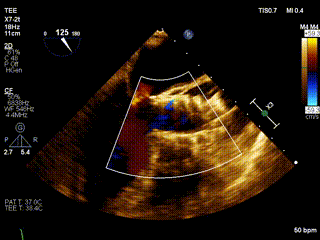

心脏超声

LVEF 35 %,主动脉瓣钙化,主动脉瓣三叶瓣,开放受限,闭合不拢,主动脉瓣峰值流速4.3m/s,峰值压差73mmHg,平均压差37mmHg,三尖瓣重度反流,TAPSE 13mm。

食道超声释放前

食道超声释放后

瓣膜释放后,食道超声及造影均提示瓣膜无残余反流。